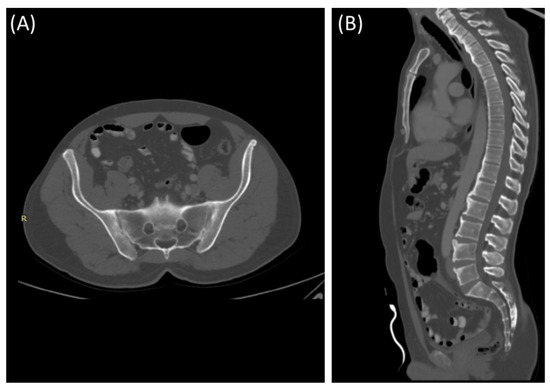

Figure 4.

Axial bone window CT scan (A) and coronal bone window CT scan (B) for a 41-year-old male presenting with Rt sciatica suggestive of bilateral sacroiliitis (same Patient as in Figure 3).

Figure 5.

Axial bone window CT scan (A) showing Chronic sacroiliitis with ankyloses of the sacroiliac and a sagittal bone window CT scan (B) showing Syndesmophytes in the spine in a 55-year-old patient with Ankylosing spondylitis.